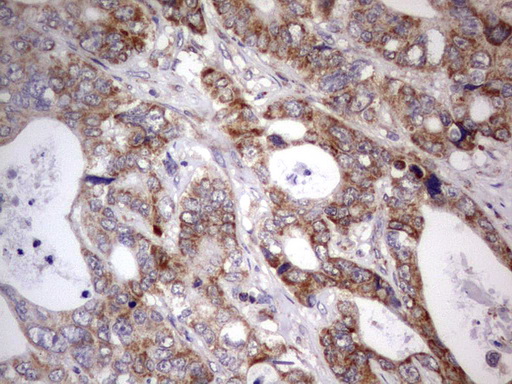

Immunohistochemical staining of paraffin-embedded Adenocarcinoma of Human colon tissue using anti-APC mouse monoclonal antibody. (M00008-2; heat-induced epitope retrieval by 1mM EDTA in 10mM Tris, pH8.5, 120°C for 3min)

Immunohistochemical staining of paraffin-embedded Adenocarcinoma of Human colon tissue using anti-APC mouse monoclonal antibody. (M00008-2; heat-induced epitope retrieval by 1mM EDTA in 10mM Tris, pH8.5, 120°C for 3min)